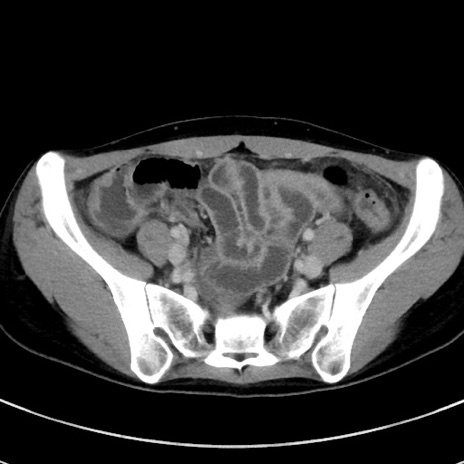

症例17(横断像)

【症例】20歳代女性

【主訴】嘔吐、下腹部痛

【現病歴】昨日夕食後に嘔吐し下腹部痛が出現。本日になっても嘔吐持続し改善しないため来院。

【身体所見】意識清明、BT 37.2℃、BP 108/67mmHg、腹部:平坦、やや硬、下腹部正中から右にかけて圧痛あり、反跳痛軽度あり、tapping pain(+)。

【データ】WBC 13600、CRP 14.94

冠状断像